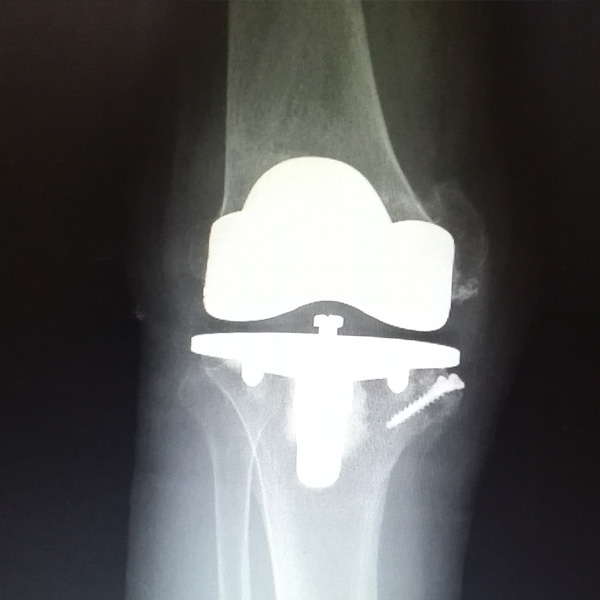

• 膝關節(jié)內翻膝關節(jié)內翻手術后手術前

膝關節(jié)內翻

患者劉某某,女66歲,左側膝關節(jié)嚴重內翻(俗稱的“羅圈腿”),疼痛到不能生活自理。經平臺推薦到哈爾濱醫(yī)科大學附屬第二醫(yī)院骨關節(jié)科就診,......